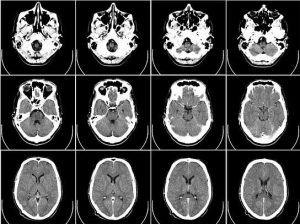

“Se utilizaron cerca de 400 muestras cerebrales post mortem de enfermos de Alzheimer, así como 100 PET de personas que viven con la enfermedad para rastrear la acumulacion de tau, una de las dos proteínas clave implicadas en la afección”.

Entre las características de la enfermedad de Alzheimer, se suele observar que tau y otra proteína llamada beta amiloide se acumulan en nudos y placas (conocidos ambos como agregados) que matan las células cerebrales y encogen el cerebro.